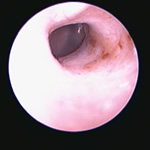

角化症、脂漏症という生まれつきの体質を持ったワンちゃんは耳垢が多くなりがちです。また、角化症、脂漏症の長毛種となれば、耳の中に毛が生えた犬種も多く耳道から耳垢を排泄しにくくなります。それらが原因で耳に汚れがたまります。また長毛種はトリミングに行く回数も多く、耳を洗う機会が多くなります。こんな負の連鎖があり、いずれも耳を悪くする大きな原因になります。その全ての要因に対処しなければ耳の病気は解決しません。写真は鼓膜手前に耳垢や毛が蓄積し、通常の耳洗浄ではきれいにできない状態です。セカンドオピニオンで来院されるワンちゃんで最も多い病気の1つです。

フレンチブルドックはアトピー性皮膚炎、食物アレルギー、脂漏症、甲状腺機能低下症など皮膚病になりやすい犬種です。さらにフレンチブルドックの耳道はもともと入口がとても広く、鼓膜手前で極端に狭くなっています。もし、これらの皮膚病を発症すると外耳炎が起こりやすくなります。外耳炎が起こると耳垢が溜まり、耳洗浄による耳道刺激があったり、微生物の増殖など負のサイクルに陥ることがあります。さらに耳道周囲の体毛が耳の中に入りやすいため、鼓膜手前に毛が蓄積します(写真)。体毛、微生物が増殖した耳垢、皮膚病の放置といった悪化因子が重なると非常に重度の中耳炎になります。